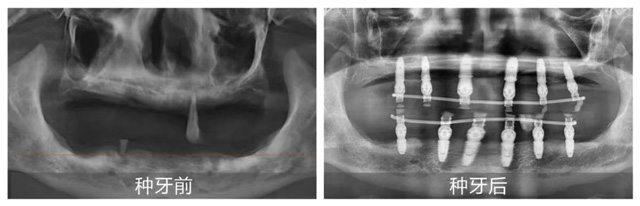

考虑到熊叔叔年龄较大且患有高血压,全口种植风险大、术后反应强,张洁为其制定半口种植方案。手术在家人陪伴下顺利结束,熊叔叔当天就戴上临时牙冠,恢复基础饮食功能。他激动地道,“这次终于种上了,原来种牙这么舒适,我根本不用操心,医护人员领着我检查,医生做手术我都没什么感觉。想到晚上就能吃东西,我太激动了。”